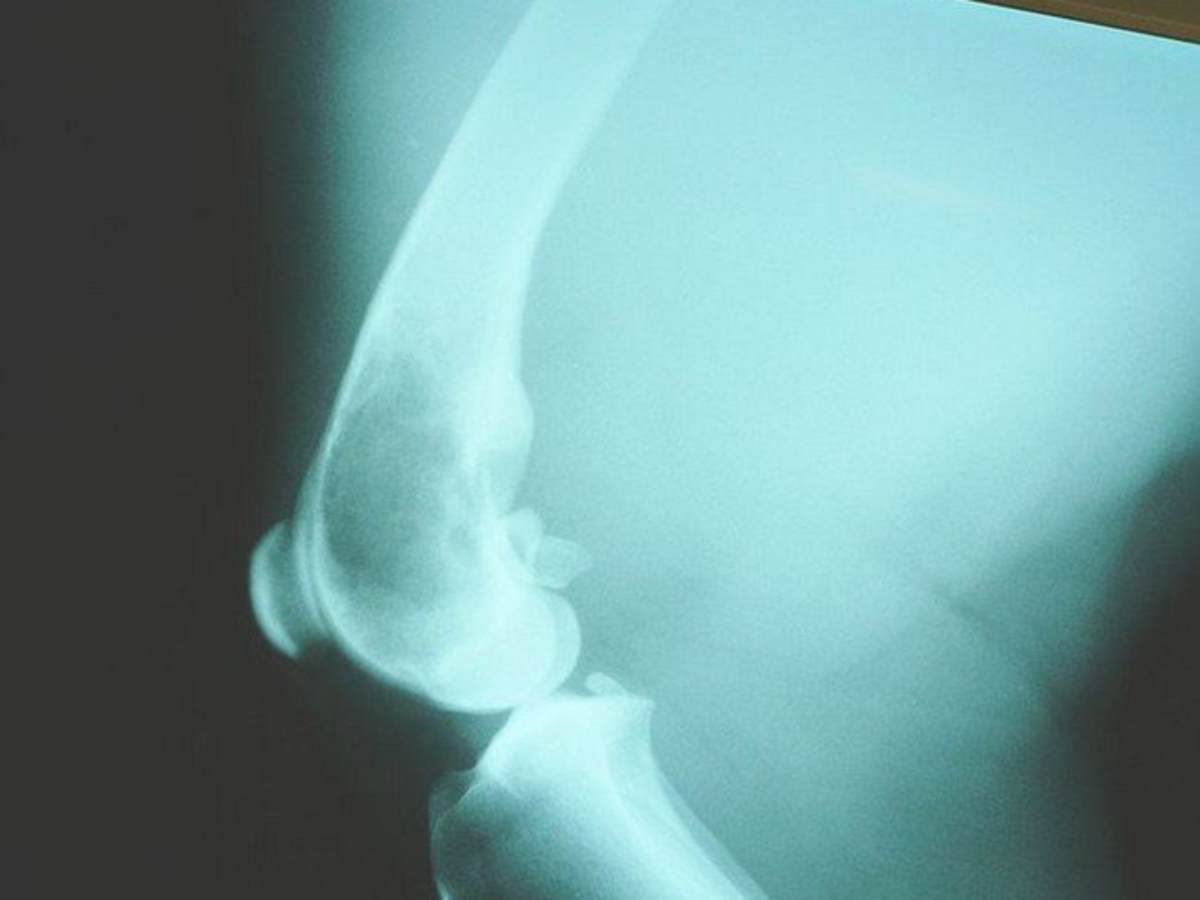

Get Femur Bone Cancer Symptoms Pictures. Bone cancer destroys normal bone tissue. A bone tumor is a neoplastic growth of tissue in bone.

Bone And Soft Tissue Tumors Of Hip And Pelvis Sciencedirect

Start studying n311 gi, bones, cancer. If cancer is diagnosed, relieving symptoms remains an important part of cancer care and treatment. This disease affects the body's skeletal system.

If cancer is diagnosed, relieving symptoms remains an important part of cancer care and treatment. Secondary bone cancer is more common. They form directly in the bones or surrounding tissue, such as cartilage. Read on and learn what they are!